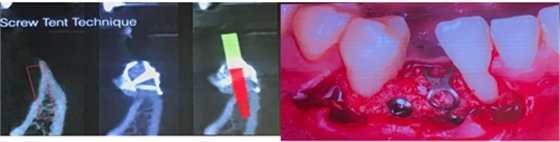

(一)針對下頜前牙區(qū)牙槽嵴嚴(yán)重骨吸收的患者,教授提出可以應(yīng)用植骨釘加不可吸收膜帳篷技術(shù)進(jìn)行水平向的骨增量: